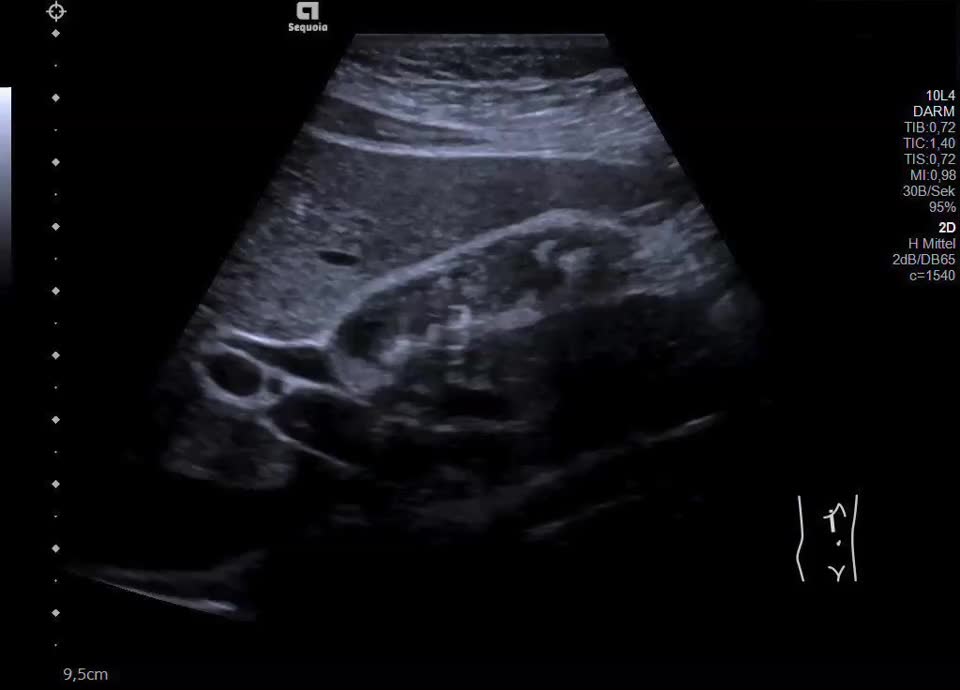

16-jährige Patientin berichtet seit mehreren Monaten über rezidivierende Durchfälle und Bauchschmerzen im Bereich der rechten Colonflexur, zuletzt etwa alle 14 Tage. Vor zwei Monaten wurde sie nach einer besonders starken Episode in die Klinik überwiesen; Labor unauffällig. Zum Zeitpunkt der letzten Untersuchung beschwerdefrei. Sonographisch zeigt sich eine Wandverdickung der Gallenblase mit inhomogener Schichtung bei erhaltener, glatter Innen- und Außenkontur. Betroffen sind vor allem Fundus und Corpus, das Infundibulum erscheint unauffällig. In den verdickten Wandabschnitten finden sich hyperechogene Einzelechos mit Reverberationsartefakten (Kometenschweifartefakte). Zusätzlich zeigen sich in der Hochfrequenzsonografie (Video) echofreie, kleinzystische Areale in der Wand, die den erweiterten Rokitansky-Aschoff Sinus entsprechen. Charakteristischer Befund einer segmentalen Gallenblasenadenomyomatose.